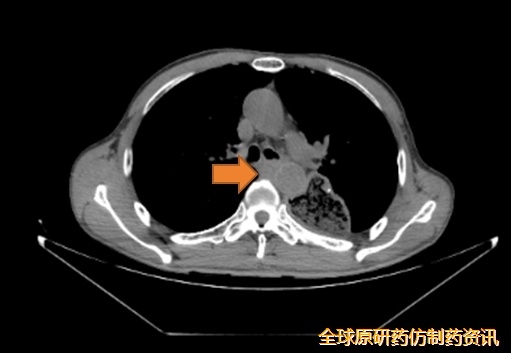

2024-07-10,PET-CT示:左侧胸腔胃,吻合口区FDG代谢未见增高;后纵膈不规则形软组织影,FDG代谢异常增高,SUVmax=7.6,与气管、降主动脉、胸椎前缘界限模糊,前方气管受压、向气管内突入,考虑食管癌术后转移,累及气管、降主动脉、胸椎前缘。

图1 影像学检查(2024-07-10)

2024-07-23开始行后纵隔转移灶及左主支气管近端转移灶姑息性放疗,DT 50Gy/25F。

图3 患者接受灶姑息性放疗